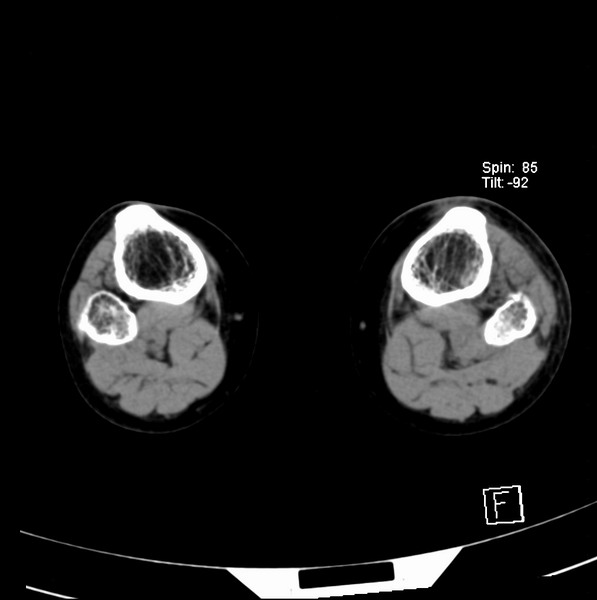

标题: CT21917:右腓骨小头是否骨软骨瘤? [打印本页]

标题: CT21917:右腓骨小头是否骨软骨瘤?

女、43.

不是骨软骨瘤,“牵拽征”,正常变异。有平片吗?

正常变异,“牵拽征”,比目鱼肌牵拽.

比目鱼肌附着点